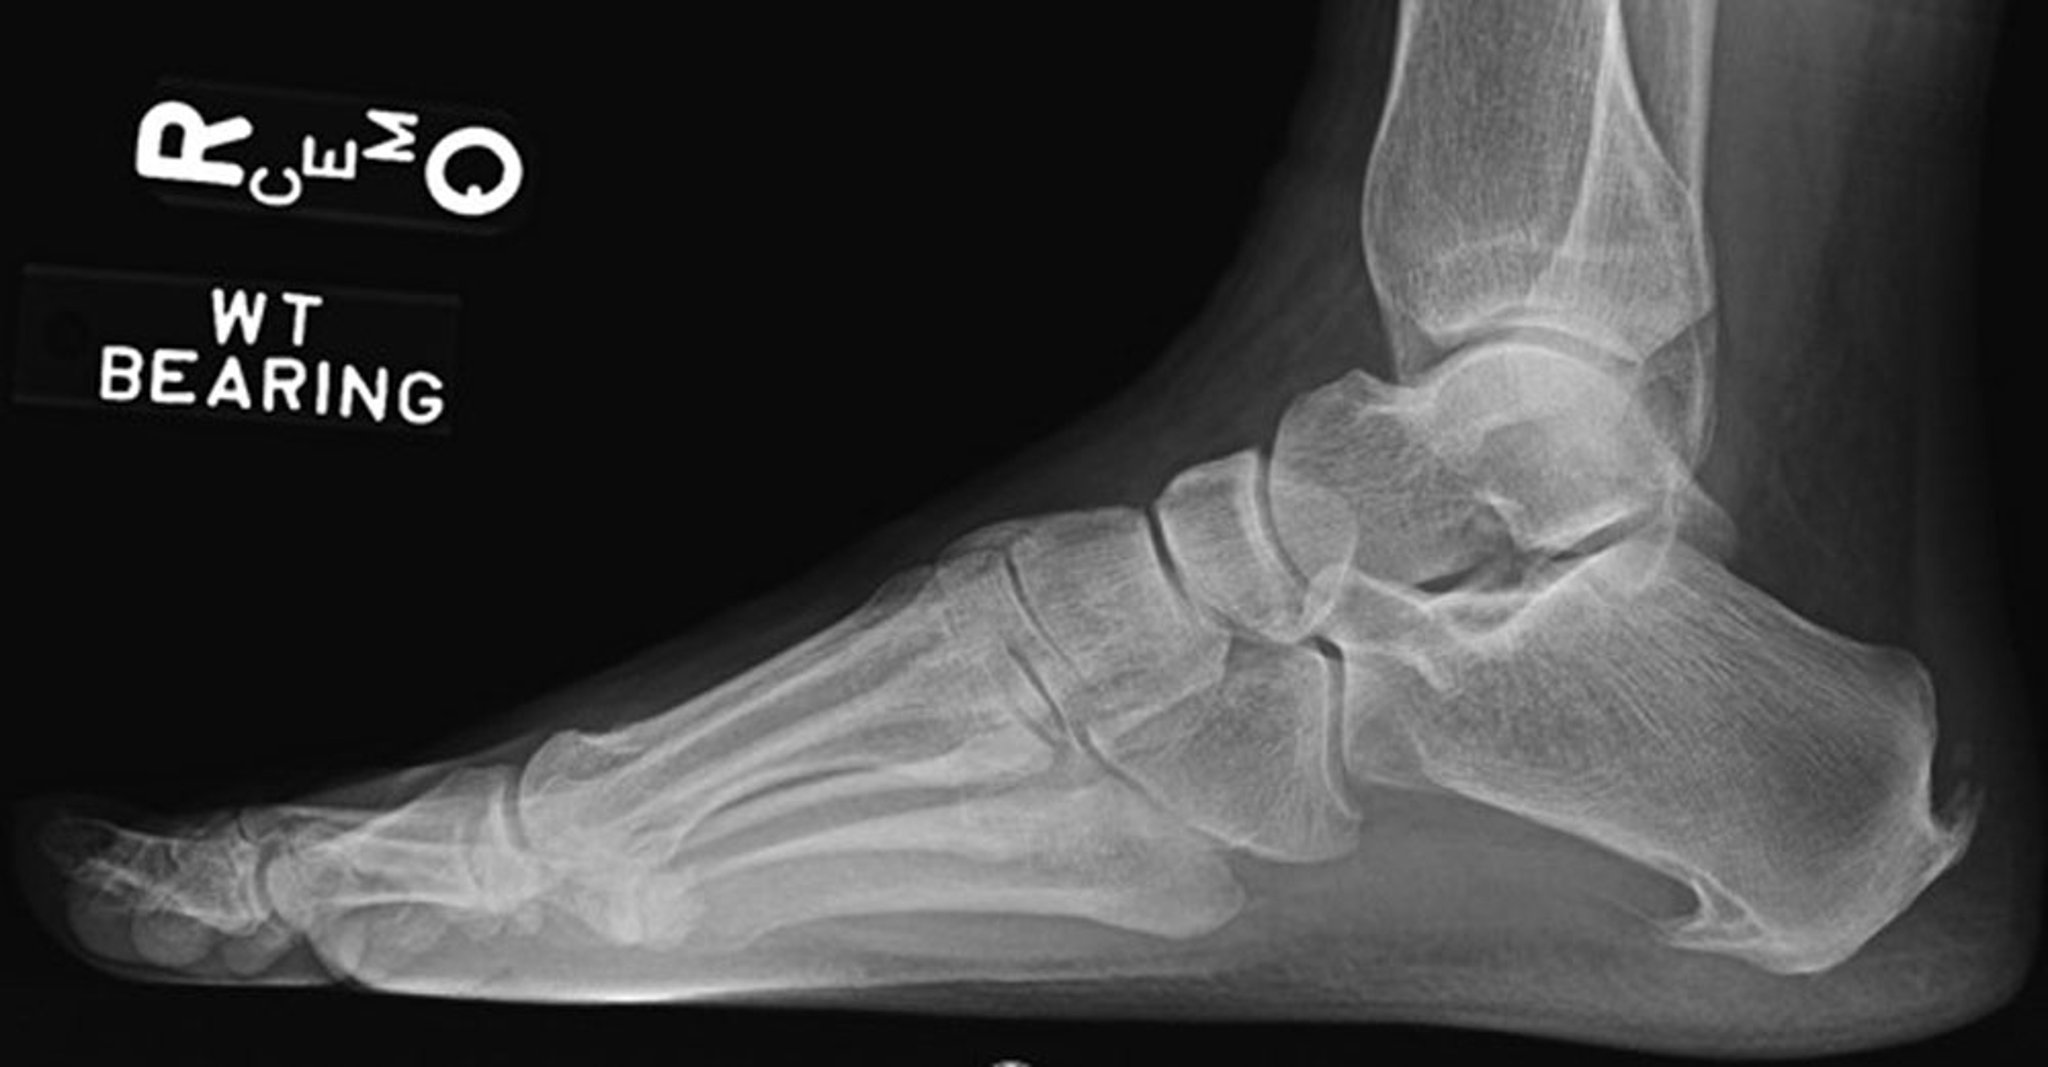

联合性足底与跟骨骨刺

侧位X线片显示跟腱附着处有联合足底和后跟骨骨刺。

Image courtesy of James C.Connors, DPM.